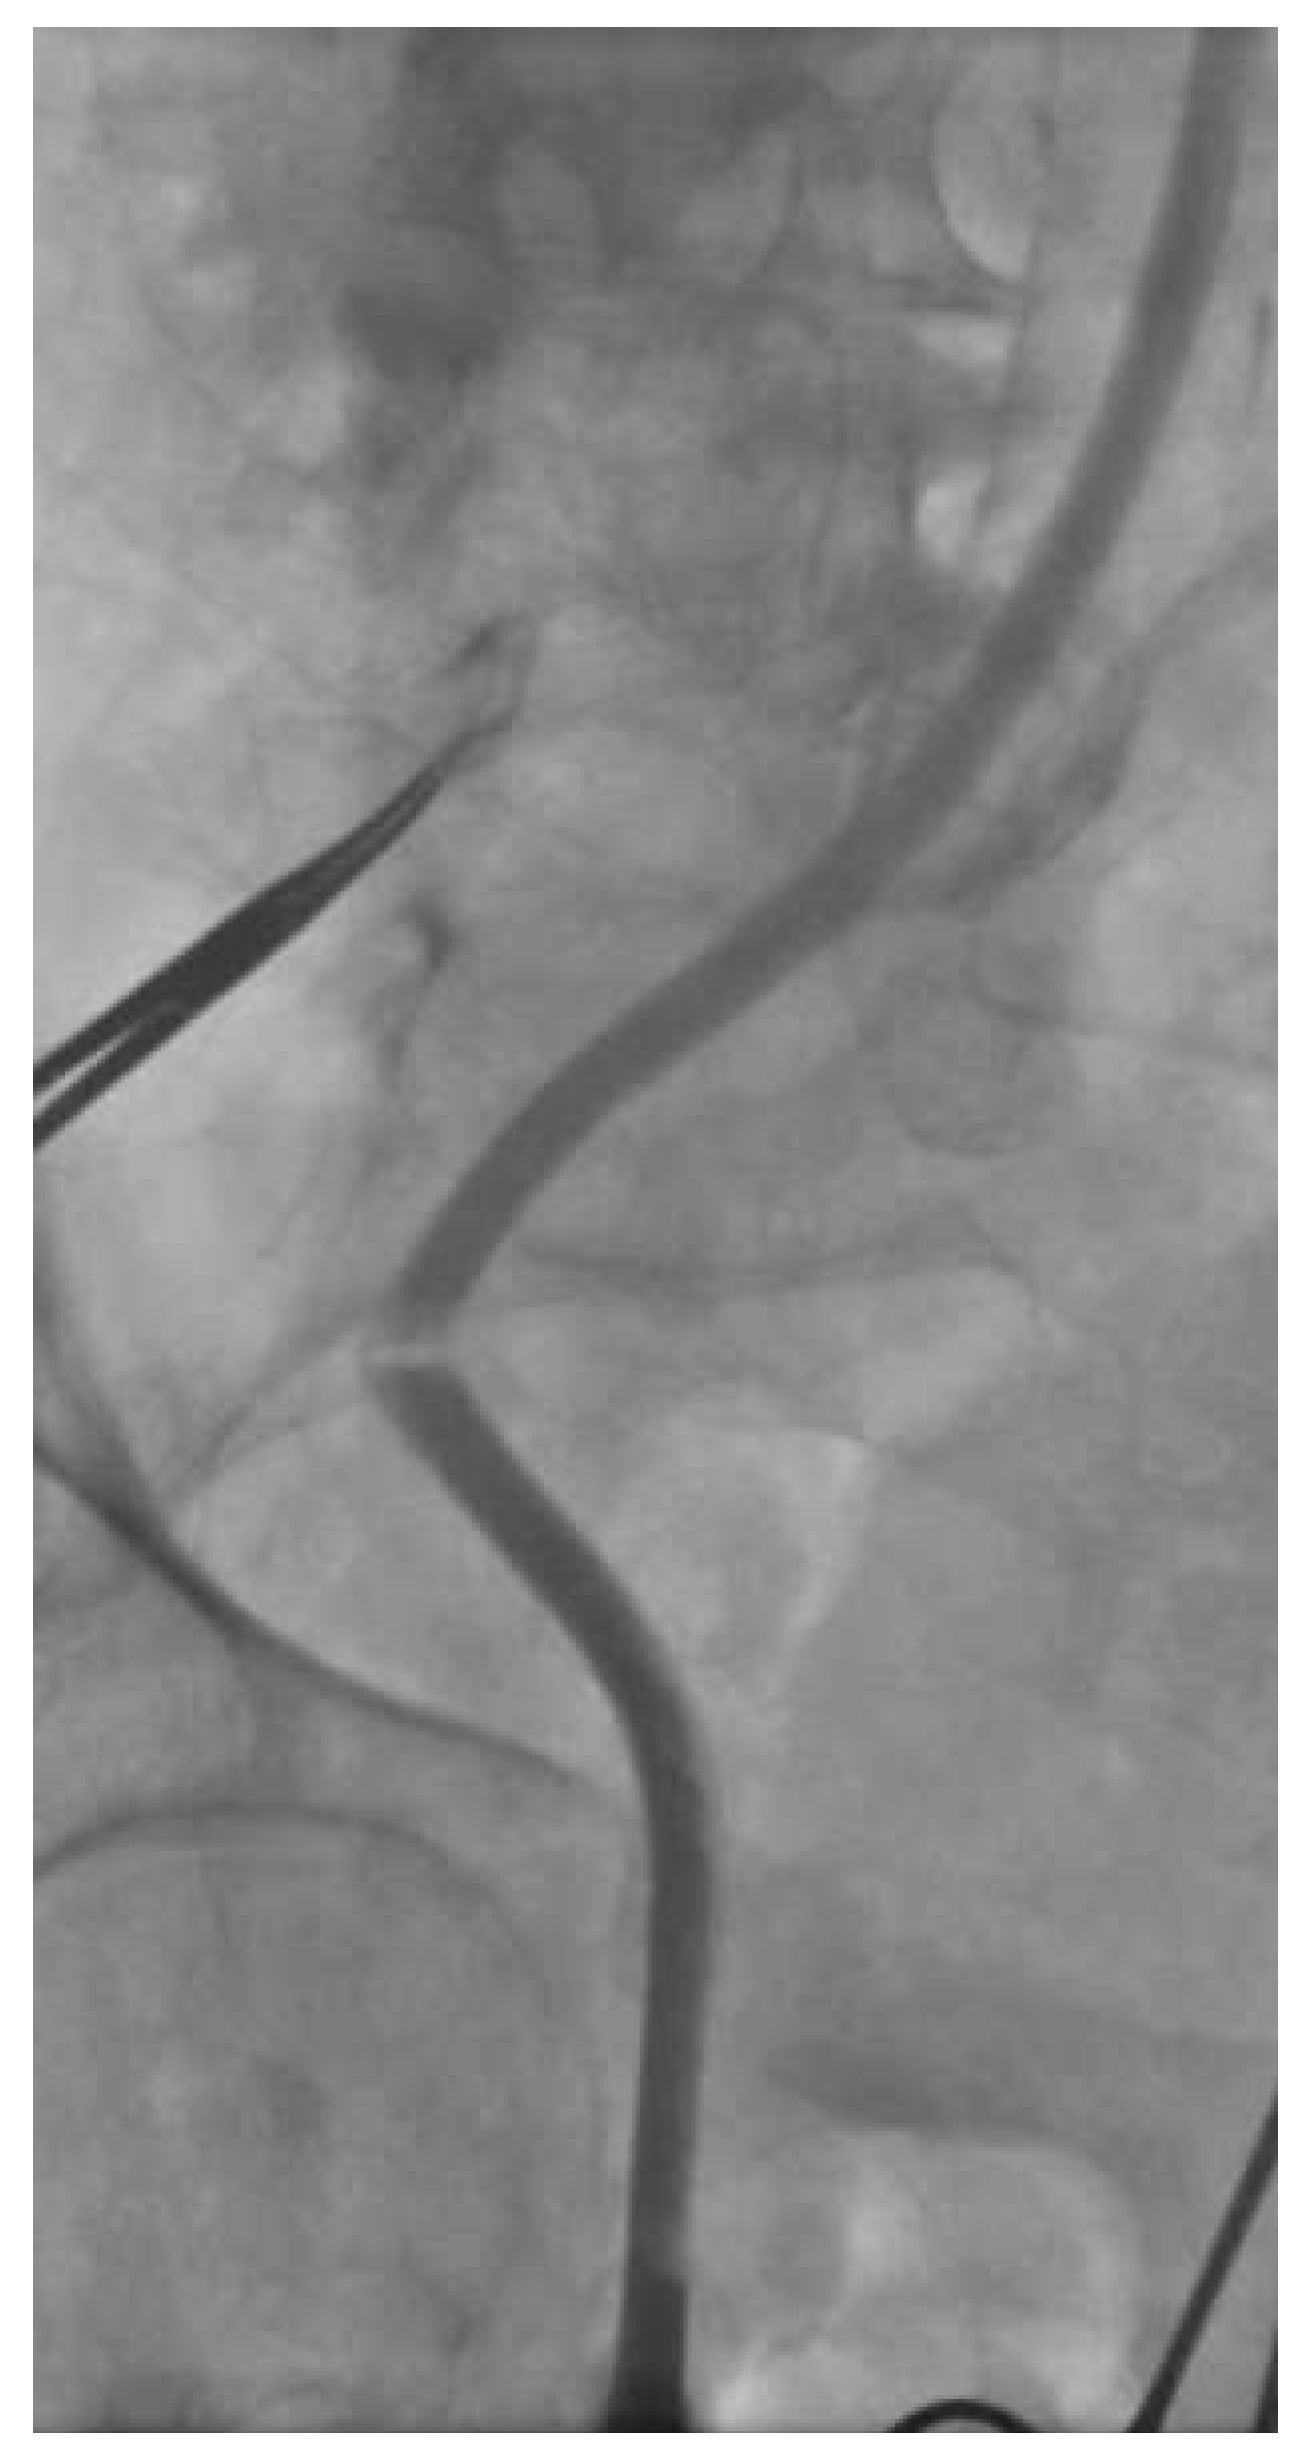

A 91-year-old active patient, who had been followed for several years for critical aortic stenosis (mean gradient of 60 mm Hg, normal left ventricular ejection fraction, valve area of 0.6 cm2) with mild symptoms, was admitted for overt heart failure. The coronary angiogram did not show any significant coronary artery lesions while the left–right heart catheterisation confirmed the severity of the aortic stenosis. The logistic EuroSCORE and the STS (Society of Thoracic Surgeons) scores were 11.4 and 4.4% risk of mortality, respectively. Considering the frailty of this nonagenarian, the heart team decision was to propose transfemoral TAVR since the ilio-femoral vascular access was considered suitable. Indeed, the minimum diameter at ilio-femoral angiography was around 8 mm, while moderate vessel tortuosities were present (Figure 2).

Under local anaesthesia and conscious sedation, we punctured the common femoral artery and performed the pre-closure technique using the Prostar® XL10 (Abbott Vascular, Reedwood City, CA). Over a Super Stiff ST-1 wire (Boston Scientific, Maple Grove, MN, USA) we inserted a folded 19-French SoloPath® sheath without any difficulties. As recommended by the instructions for use, once the sheath was full inserted we inflated the sheath balloon at 20 atmospheres for one minute. As we commonly did with other large-bore sheaths, the stiff wire was retrieved simultaneously with the dilator. At this time we noticed a kink in the sheath at the level of the iliac tortuosity (Figure 3), this kink was overcome with some difficulty by advancing a 0.035” wire. Subsequently, the kinked portion of the sheath was dilated with a peripheral balloon catheter (Admiral Xtreme 7 × 40 mm; Medtronic, MN, USA) (Figure 4). However, since we were not satisfied with that aspect of the sheath and we feared difficulties in advancement or retrieval of equipment during the procedure, we preferred to exchange the SoloPath® sheath for an 18-F Cook sheath (Cook Medical, Bloomington, IN, USA), which completely straightened the vessel (Figure 5). The procedure was then completed by pre-dilatation and successful implantation of a 29 Medtronic CoreValve®. The final ilio-femoral angiography from the contralateral femoral access showed no vascular complication or bleeding.

Figure 2. Right ilio-femoral access before large sheath insertion with moderate tortuosity and mild calcification.